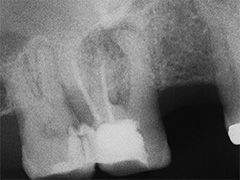

Dieser Zahn wurde schon geraume Zeit zuvor von einer Kollegin im Notdienst eröffnet und anschlies­send mit einer aufwendigen Amal­gamrestauration ästhetisch an­sprechend wieder verschlossen. (Bild 1) Uns blieb noch WK/WF, was bei massiver Überstopfung der hin­teren Wurzel auch gelang (Bild 2).

"Überstopfen ist immer noch besser als Unterstopfen" laut Koçkapan. OK, hier wurde des Guten aber ganz eindeutig zuviel getan.

Also direkt neben dem Zahn das Zahnfleisch ein wenig angehoben und zur Seite gedrängt und dann mit einem scharfen Löffel den Überschuss vollständig entfernt.

Schon 8 Monate später ist eine deutliche Verbesserung der Gesamt­situation unverkennbar (Bild 3). Verlorengegangene Knochensubstanz wurde in Teilen schon wieder aufge­baut, doch ist noch gar nichts entschieden. Schaun mer also ma'.

Abrechnungstechnisch hat der Mut zur WR an 38 gefehlt, deshalb nur EXZ1.